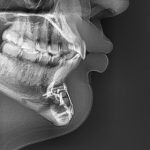

Female Custom Fronto-Temporal Head Widening Implants Case Example

Custom Fronto-Temporal Implants are patient-specific cranial implants designed to widen the upper temporal region and the lateral forehead in one continuous contour. They address the transition zone between the forehead and the side of the head — an area that strongly influences facial width and upper facial balance. What Area They Augment Fronto-temporal implants cover: Read More…